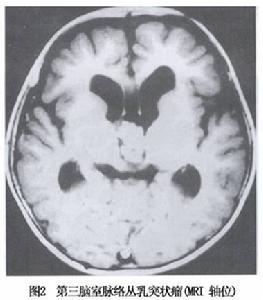

4.MRI檢查 腫瘤的MRI表現在T1加權像中呈低信號,較腦實質信號低但較腦脊液信號高;在T2加權像中呈高信號,與腦脊液分界清楚而腫瘤輪廓不規則,有些可見局灶出血、鈣化與血管流空影,腫瘤有顯著的對比增強並有腦積水(圖1,2)。